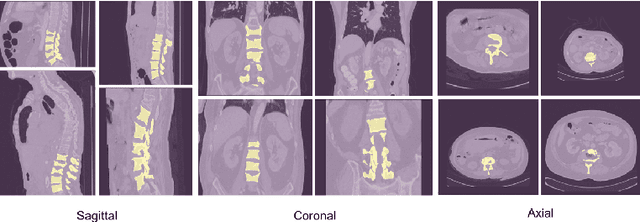

Abstract:Accurate segmentation of the vertebra is an important prerequisite in various medical applications (E.g. tele surgery) to assist surgeons. Following the successful development of deep neural networks, recent studies have focused on the essential rule of vertebral segmentation. Prior works contain a large number of parameters, and their segmentation is restricted to only one view. Inspired by DoubleU-Net, we propose a novel model named DoubleU-Net++ in which DensNet as feature extractor, special attention module from Convolutional Block Attention on Module (CBAM) and, Pyramid Squeeze Attention (PSA) module are employed to improve extracted features. We evaluate our proposed model on three different views (sagittal, coronal, and axial) of VerSe2020 and xVertSeg datasets. Compared with state-of-the-art studies, our architecture is trained faster and achieves higher precision, recall, and F1-score as evaluation (imporoved by 4-6%) and the result of above 94% for sagittal view and above 94% for both coronal view and above 93% axial view were gained for VerSe2020 dataset, respectively. Also, for xVertSeg dataset, we achieved precision, recall,and F1-score of above 97% for sagittal view, above 93% for coronal view ,and above 96% for axial view.